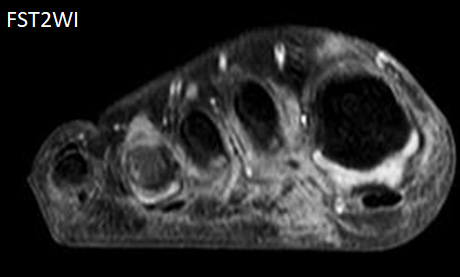

8歳男児 歩行時痛、足底部腫瘤

FST2WI sag

FST2WI

- 【参考症例】

- 画像では浸潤性の軟部腫瘍、結節状石灰化、強く不均一な増強効果